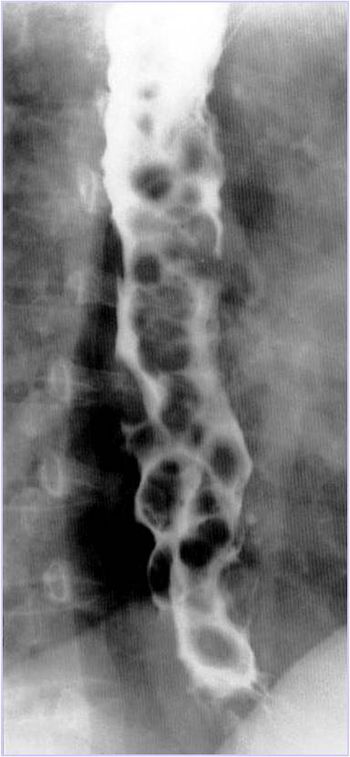

What is your diagnosis in this patient with long standing excessive alcohol intake and difficulty swallowing?